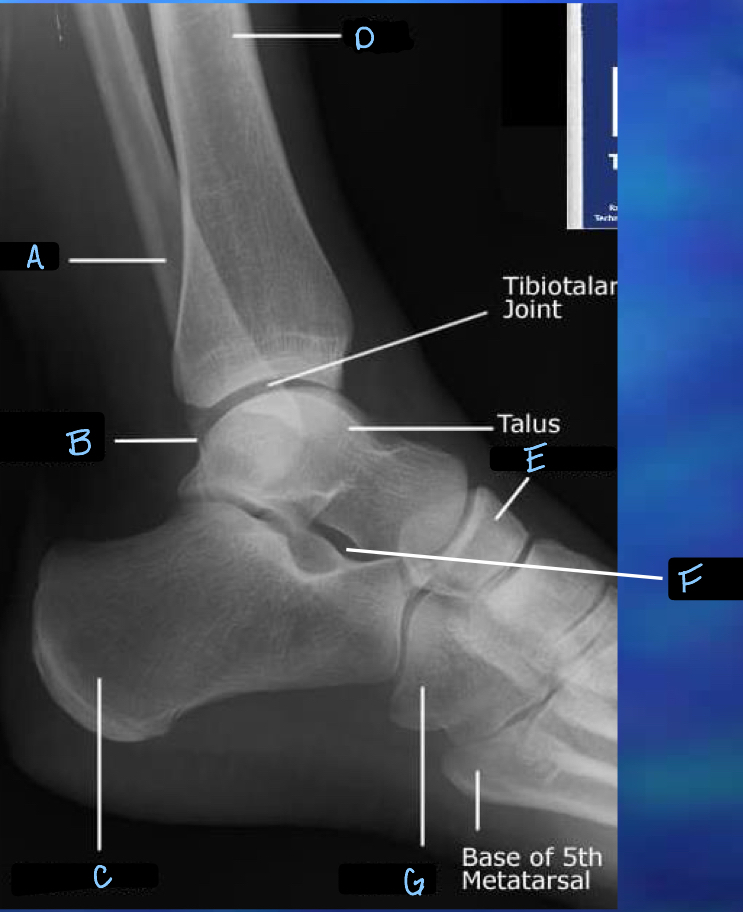

9

What is B?

10

What is C?

11

What is D?

12

What is E?

13

What is F?

14

What is G?